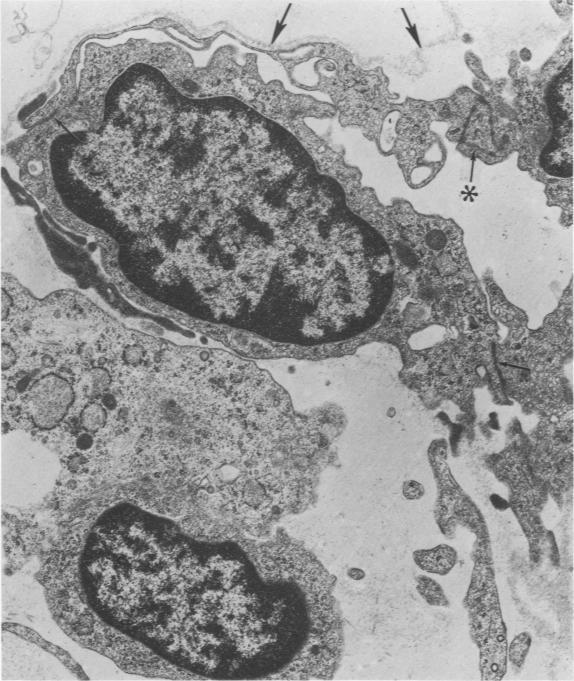

With removal of large numbers of macrophages by airway lavage, Type 1 cells were isolated in heterogeneous cell populations following the stepwise dissociation of lung tissue. Using a carefully timed collagenase-trypsin digestive sequence at 37 C, unwanted cellular and noncellular lung components were minimized prior to selective release of Type 1 cells. Resulting heterogeneous cell suspensions containing well-preserved Type 1 cells, as determined by electron microscopy, were layered onto a shallow gradient (3 to 6% Ficoll in minimal essential medium [MEM]) and separated at unit gravity into enriched subpopulations of various cell types. These included various fractions enriched with respect to Type 1 cells (70%), Type 2 cells (82%), and macrophages (81%). Identification of Type 1 cells following their isolation and gradient enrichment was established by light microscopic staining techniques and by specific cell surface characteristics in vitro as visualized by electron microscopy.

通过气道灌洗去除大量巨噬细胞后,在肺组织逐步解离后的异质细胞群体中分离出I型细胞。在37℃下使用精心定时的胶原酶 - 胰蛋白酶消化序列,在选择性释放I型细胞之前,将不需要的细胞和非细胞肺成分减至最少。通过电子显微镜测定,所得含有保存良好的I型细胞的异质细胞悬液被铺在浅梯度(最低限度基本培养基[MEM]中3%至6%的菲可)上,并在单位重力下分离成各种细胞类型的富集亚群。这些包括富含I型细胞(70%)、II型细胞(82%)和巨噬细胞(81%)的不同组分。通过光学显微镜染色技术以及电子显微镜观察到的体外特定细胞表面特征,确定了分离和梯度富集后的I型细胞。